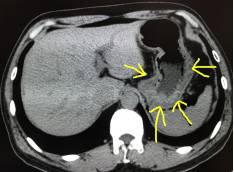

如图4:红色箭头指的就是未做胃肠道准备的患者,可见聚集的直肠明显增厚,这一段肠管很容易被认为是增厚的病变,直肠癌?这时候就要打问号了,是真正的增厚的肠管还是粪便。

这时候再看图5,同一个患者同一个部位,检查前清洁灌肠后,向肛门注入清水,可见直肠被充盈起来了,壁很薄,一点都没有增厚。所以如果单单就图4,很容易被误诊为直肠癌。这也正体现了做CT之前胃肠道准备的重要性。如果临床配合不好,做的不足,会影像CT的诊断结果。